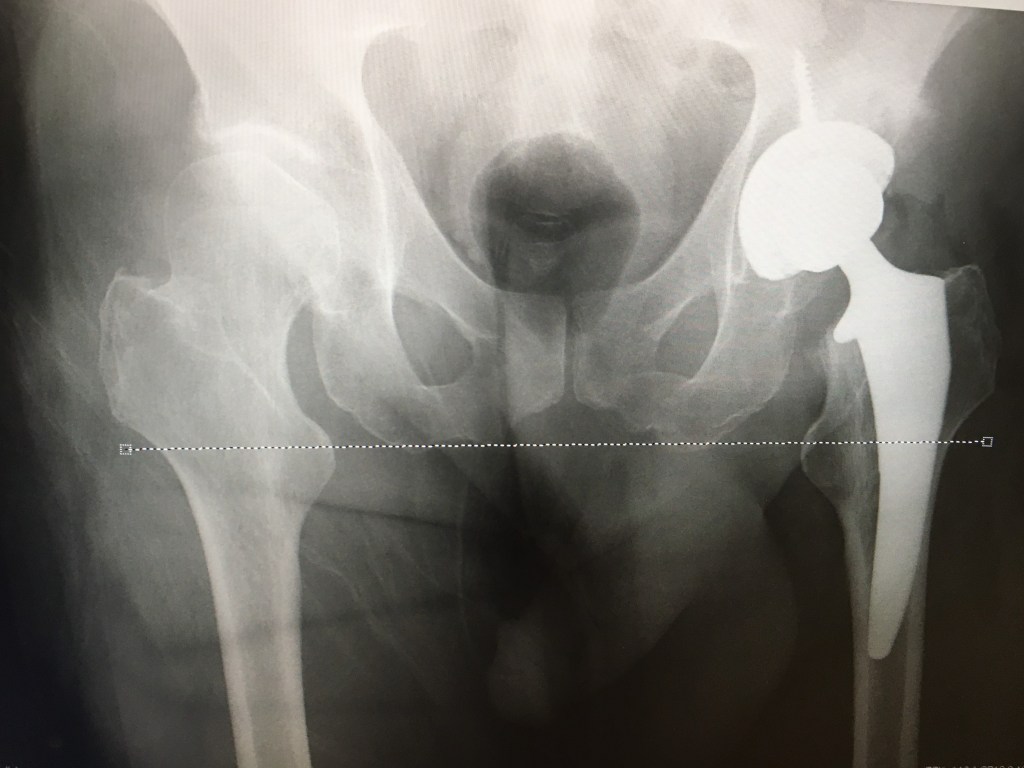

Post surgery

In the pre surgery image the right hip shows a normal layer of cartilage (at the blue arrow). The x-ray image shows this as a gap between the bones. This is completely absent in the left hip. There the cartilage has been abraded away by the arthritic femoral head. As a result the left leg bone had pushed its way up into the hip socket and was bearing bone on bone. As a result, my left leg had become shorter over time, by more than one centimeter. Post surgery, the artificial hip holds the left leg bone in its correct position. As a result, my two legs are once again the same length. The horizontal dashed white line shows that the two leg bones are aligned post surgery. A displacement of one centimeter is seen in the presurgery case (green spacer)